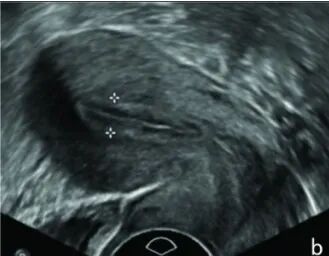

子宫内膜血流类型的评估:经阴道B超查看子宫内膜及子宫内膜下血流类型,采用Applebaum法分为三种分型:

I型:不能监测到子宫内膜血流;

II型:仅可监测到子宫内膜下血流;

III型:可监测到子宫内膜及子宫内膜下血流。

在这三种类别中,III型血流类型较其他类型更好,能让胚胎更好地着床。